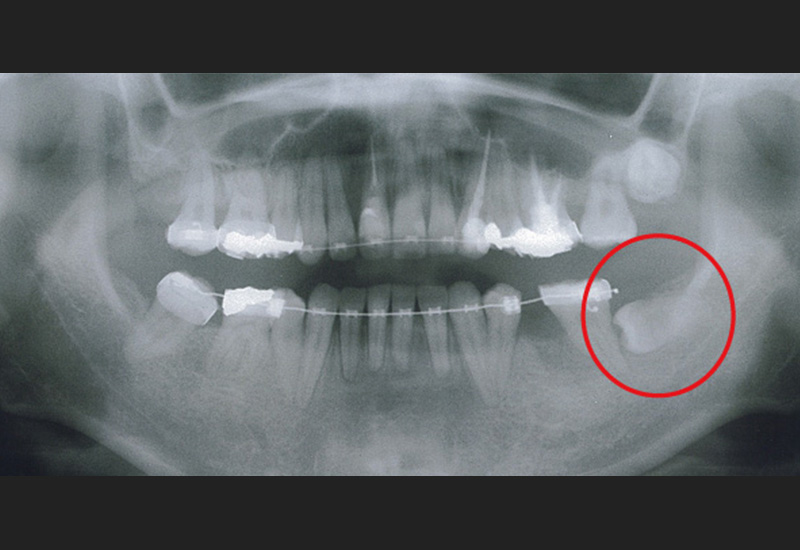

Case4 / 下右第1大臼歯欠損・下右親知らず埋伏

治療前

治療後

| 主訴 | 下右第1大臼歯欠損 下右親知らず埋伏 |

|---|---|

| 治療内容 | 倒れている下右親知らずを起こし、3D-LST矯正治療法を用い奥歯を大胆に移動。 |

| 患者年代・治療期間 | 30代女性・2年4ヶ月(難治症例) |